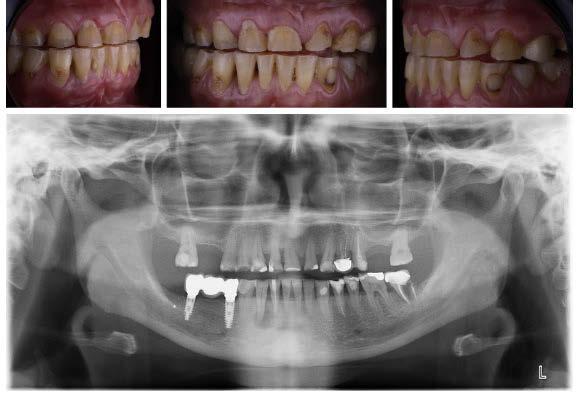

Presentamos el caso de un paciente de 66 años de edad, ASA I, que acudió a nuestra consulta para rehabilitar la arcada superior, buscando una solución definitiva para recuperar tanto la función como la estética perdida. El paciente presentaba buen estado de salud general, no refería alergias medicamentosas ni medicación relevante.

-Registros fotográficos intra y extraorales (Figura 1 a-c).

-Estudio radiográfico inicial (ortopantomografía y radiografías periapicales) (Figura 2).

A partir del estudio radiológico y de las imágenes fotográficas podemos observar edentulismo de 17, 15, 14, 12,

Figura 1a. Foto intraoral frontal inicial.

Figura 1b. Foto intraoral lateral izquierda inicial.

Figura 1c. Foto intraoral lateral derecha inicial.

Figura 2. Ortopantomografía inicial.

25, 26, 28, 37, 38, 47 y 48. Presentaba corona desajustada en 13 con extensión en 12, implantes en 35-36, 45-46, con coronas ferulizadas en 35-36, 45-46, y dientes anteriores superiores con enfermedad periodontal Grado IV.

El paciente presentaba biotipo periodontal grueso, con márgenes asimétricos, con recesiones gingivales a nivel de 11 y 13 y pérdida de tejidos blandos interproximales.

3. Exploración de tejidos duros

En la exploración radiográfica (OPG, CBCT) observamos la existencia de pérdida ósea interproximal, lesión apical a nivel de la raíz mesial del 27 y el cordal del primer cuadrante incluido y neumatización sinusal del primer y segundo cuadrante.

En el CBCT observamos pérdida ósea posterior superior debida a la neumatización de los senos maxilares izquierdo y derecho. También podemos observar disponibilidad ósea apical suficiente en dientes antero-superiores para la realización de una Implantología inmediata y corticales vestibulares y palatinas conservadas.